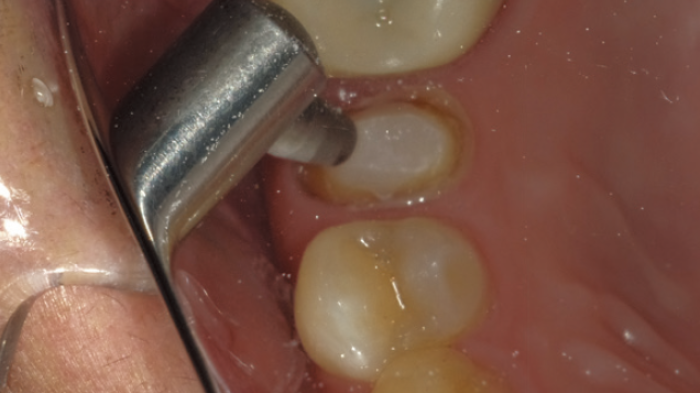

Traitement de sablage sur l'ancrage. La surface de l'ancrage peut être agrandie ; le ciment temporaire peut être complètement éliminé. Il est difficile de nettoyer l'ancrage uniquement avec des outils manuels.